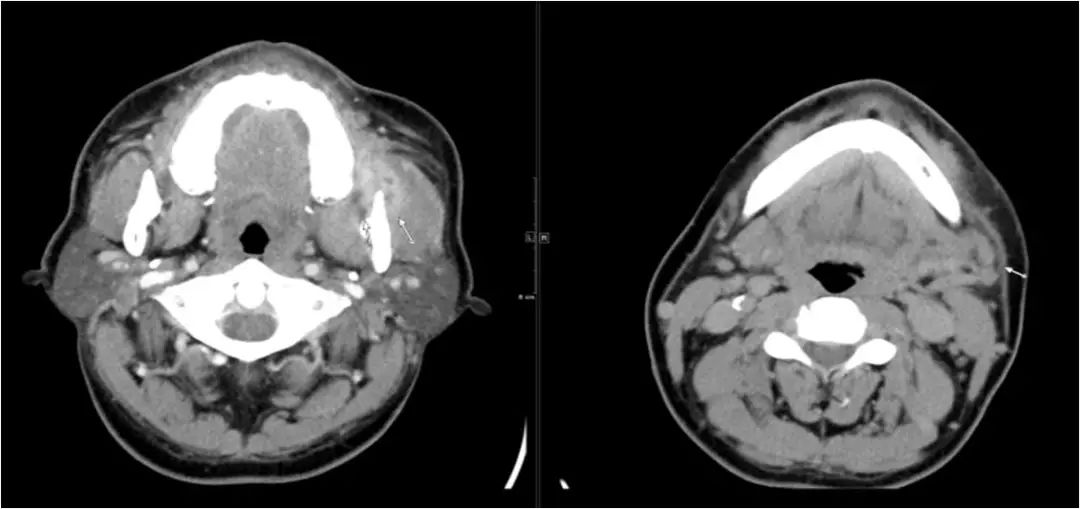

02 咀嚼肌间隙、翼下颌间隙、颊间隙

男,31岁,患者约3天前出现右侧面部口角区局限性肿胀,无明显触压痛,既往右侧下颌后牙区阵发性锐痛,曾自行口服消炎药处理,自诉牙痛症状无明显缓解,约3天前牙痛症状加重,伴夜间痛,后自觉右侧面部肿胀,约2天前开始发热,体温39.8℃。